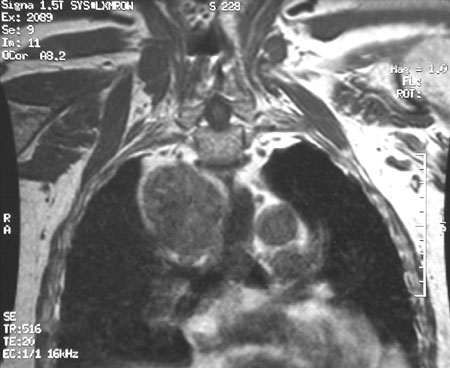

Here in coronal view is a T1 weighted MRI scan of the chest that reveals a large mass of the mediastinum that proved to be a thymoma.